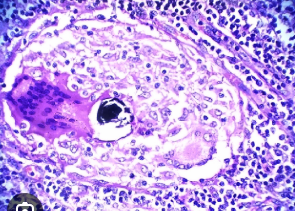

Paciente llega con un cuadro pulmonar multisistémico. En la RX observas adenomegalias parahiliares & Granulomas no caseificados.¿que esperas encontrar histologicmanete?

A

Sarcoidosis

Restrictiva Granulomatosa

Cuerpos de Schumman & Asteroides

Granuloma - histiocitos/macros epitelioides